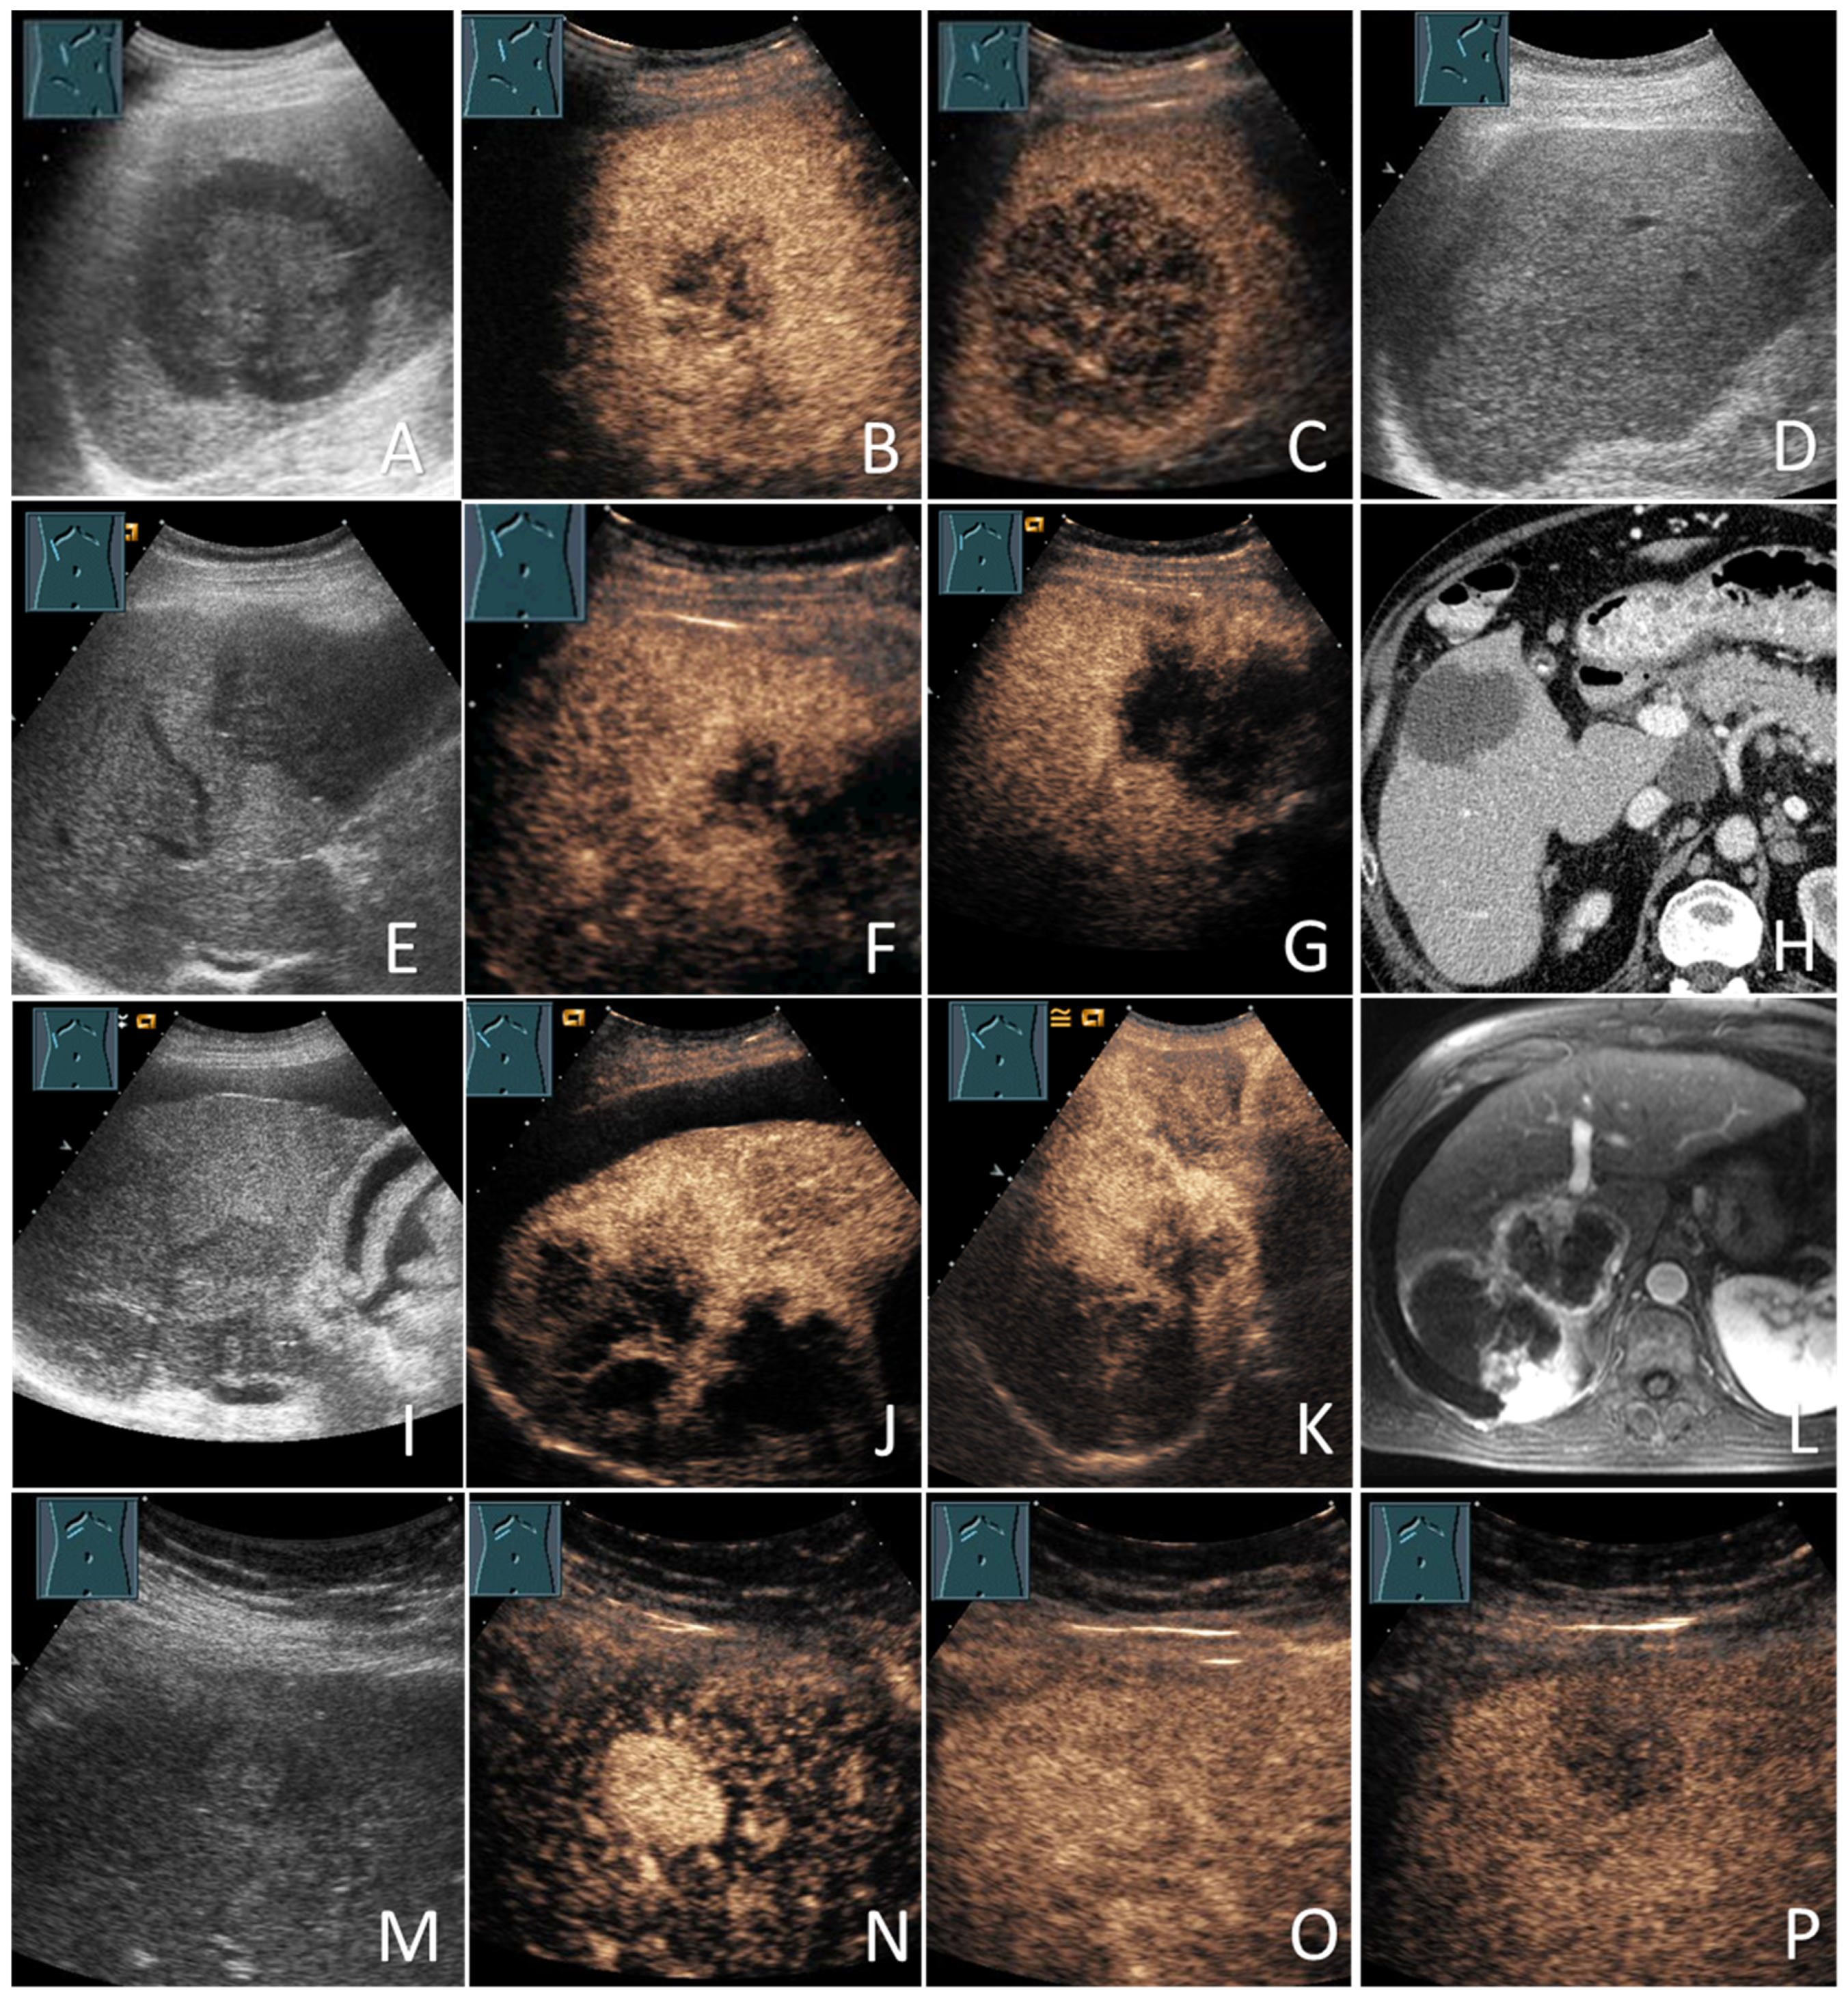

In the cases of HCC, the diagnoses were based on histology in 73/132 patients (55.3%) and the diagnostic radiological criteria in 59/132 patients (44.7%). All non-HCC mFLLs were diagnosed based on histology (22/22; 100%). Of the 71 bFLLs, 8 (11.3%) were diagnosed using histology and the remaining 63 (88.7%) were diagnosed using characteristic CEUS (e.g., hemangiomas) or sonographic appearance (e.g., simple cysts) [20,21]. The benign nature of these FLLs was further supported by cross-sectional imaging and/or sonographic FUs in 61/71 patients (85.9%), with a mean FU duration of 35.6 ± 25.5 months. Figure 1 provides information about the verification of the diagnoses of all study participants. Figure 2 and Figure 3 show some examples of the benign and malignant FLLs that were included in this study.

Figure 2.

Benign focal liver lesions (bFLLs) in patients with liver cirrhosis (LC). Liver cyst (A–D): hypoechoic FLL with multiple septa on grey-scale ultrasound (A); hypoechoic FLL with arterial phase isoenhancement of the septa (B); hypoechoic FLL without washout in the delayed venous phase (C); the corresponding CT of the FLL (courtesy of Prof. Dr. Andreas H. Mahnken, Department of Radiology, University Hospital Marburg) (D). Focal fat sparing (E–H): hypoechoic FLL on grey-scale ultrasound (E); hypoechoic FLL with isoenhancement on the arterial phase (F); hypoechoic FLL with isoenhancement on the delayed venous phase (G); the corresponding CT of the FLL (courtesy of Prof. Dr. Andreas H. Mahnken, Department of Radiology, University Hospital Marburg) (H). Regenerative nodules (I–L): large central isoechoic lesion on grey-scale ultrasound (I); large central isoechoic lesion with isoenhancement on the arterial phase (J); large central isoechoic lesion with isoenhancement on the delayed venous phase (K); the corresponding MRI of the FLL (courtesy of Prof. Dr. Andreas H. Mahnken, Department of Radiology, University Hospital Marburg) (L). Hemangiomas (M–P): large central echogenic lesion on grey-scale ultrasound (M); large central echogenic lesion with nodular enhancement on the arterial phase (N); large central echogenic lesion with isoenhancement on the venous phase (O); the corresponding MRI of the FLL (courtesy of Prof. Dr. Andreas H. Mahnken, Department of Radiology, University Hospital Marburg) (P). The lesions remained stable over a follow-up period of over 92 months.